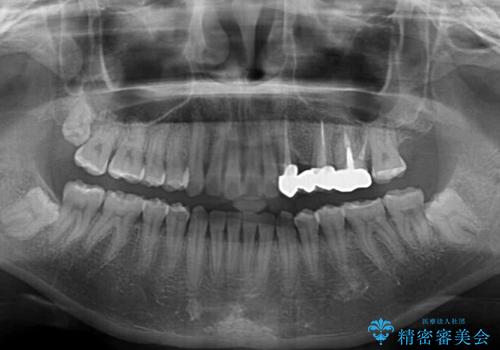

捻れた前歯と銀歯のブリッジを治したい ワイヤー矯正とオールセラミックブリッジ

矯正治療後には切断したブリッジをオールセラミックブリッジに置き換えることとしました。

矯正治療中に上下前歯が接触しない時期があり、咬み合わせ改善のために期間がかかるのではないかと懸念されましたが、結果的には補綴治療も含めて1年以内の短期間で終えることができました。